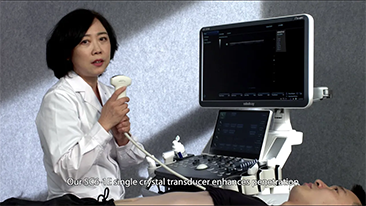

Mindray Resona General Imaging solutions help clinicians realize more accurate and efficient diagnosis and treatment results through comprehensive subdivision application probes and efficient clinical application tools.